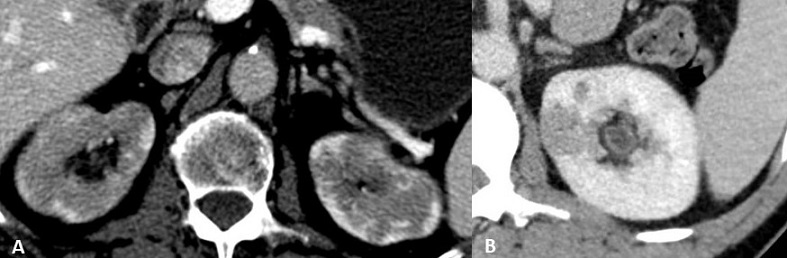

Tras el tratamiento las lesiones pueden desaparecer y condicionar una cicatriz cortical residual.(13) Aunque la NTI no tratada de tiempo de evolución puede ocasionar enfermedad renal crónica irreversible que se manifestará en las pruebas de imagen como un adelgazamiento del espesor cortical irreversible.(1) (Figura 2)

f2

Figura 2. TCMD. A, B y C: Lesiones hipodensas corticales renales en paciente con afectación renal por ER-IgG4 antes de iniciar tratamiento corticoideo. D, E y F: Resolución de las lesiones tras tratamiento con corticoides con disminución del espesor cortical residual